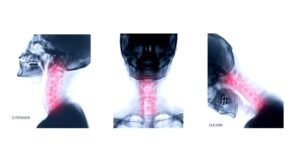

Образни изследвания като рентгенография, компютърна томография (CT) или ЯМР могат да покажат дегенеративни промени или промени в ставите между прешлените.

фасетни стави при образно изследване